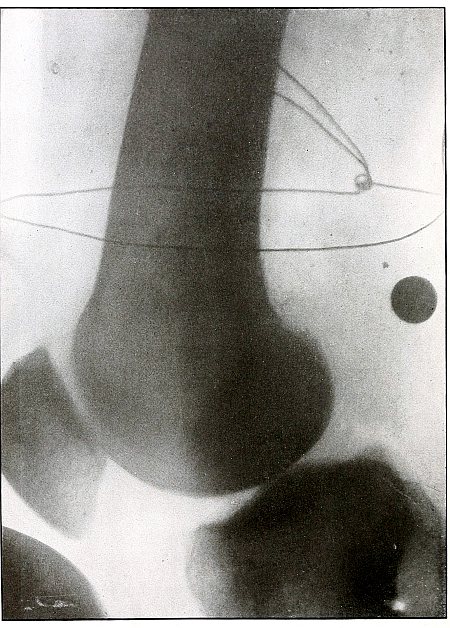

| 59. |

Gunshot wound, knee |

128 |